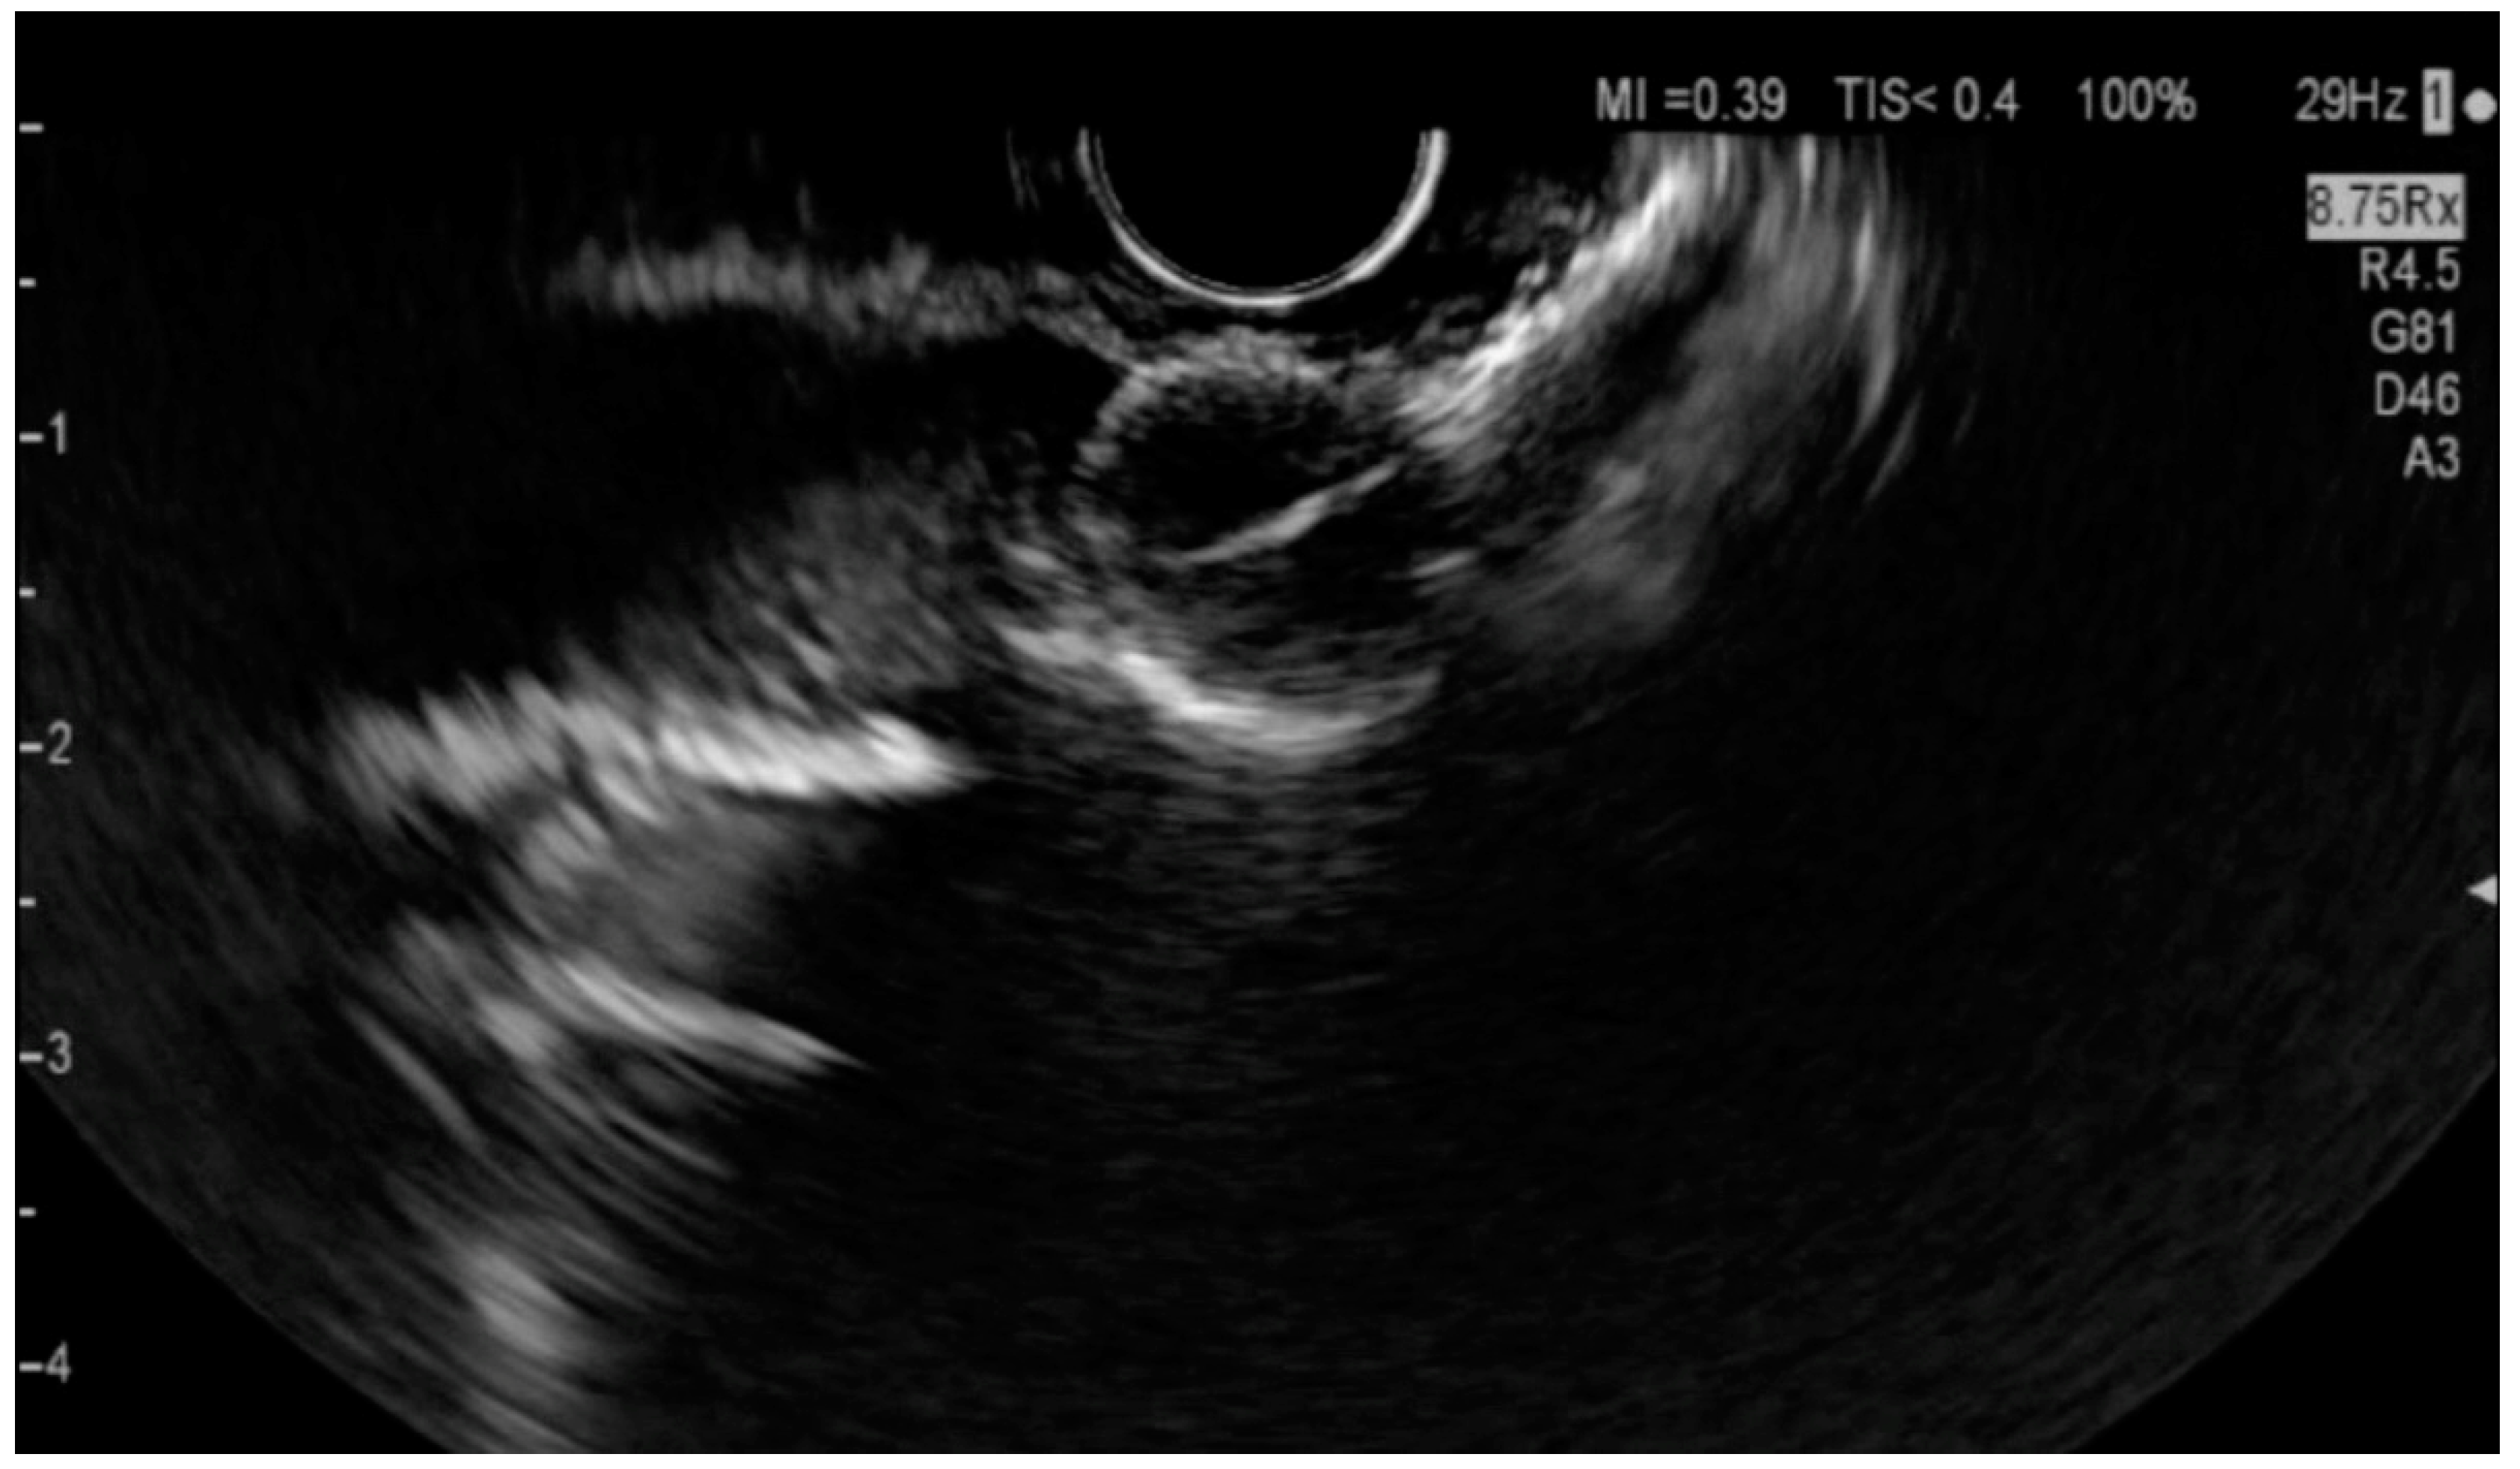

6.4.1. Endoscopic Ultrasound (EUS)

6.4.4. Intraductal Ultrasonography (IDUS)